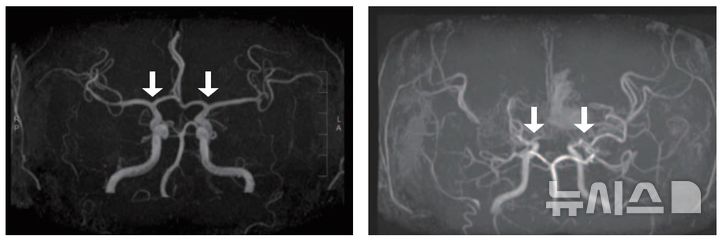

![[서울=뉴시스] 정상(왼쪽) 및 모야모야병 환자의 뇌혈관. (사진= 서울대병원 제공)](https://img1.newsis.com/2025/11/06/NISI20251106_0001985517_web.jpg?rnd=20251106085508)

[서울=뉴시스] 정상(왼쪽) 및 모야모야병 환자의 뇌혈관. (사진= 서울대병원 제공)

소아 모야모야병은 뇌로 혈액을 공급하는 혈관이 특별한 원인 없이 점차 좁아지는 만성 진행성 뇌혈관질환이다. 이 질환이 있으면 부족한 혈류를 보충하기 위해 비정상적인 미세혈관이 형성되는데, 이들은 혈류를 충분히 공급하기 어렵고 파열되기 쉬워 뇌경색·뇌출혈 등 소아 뇌졸중을 유발할 수 있다.